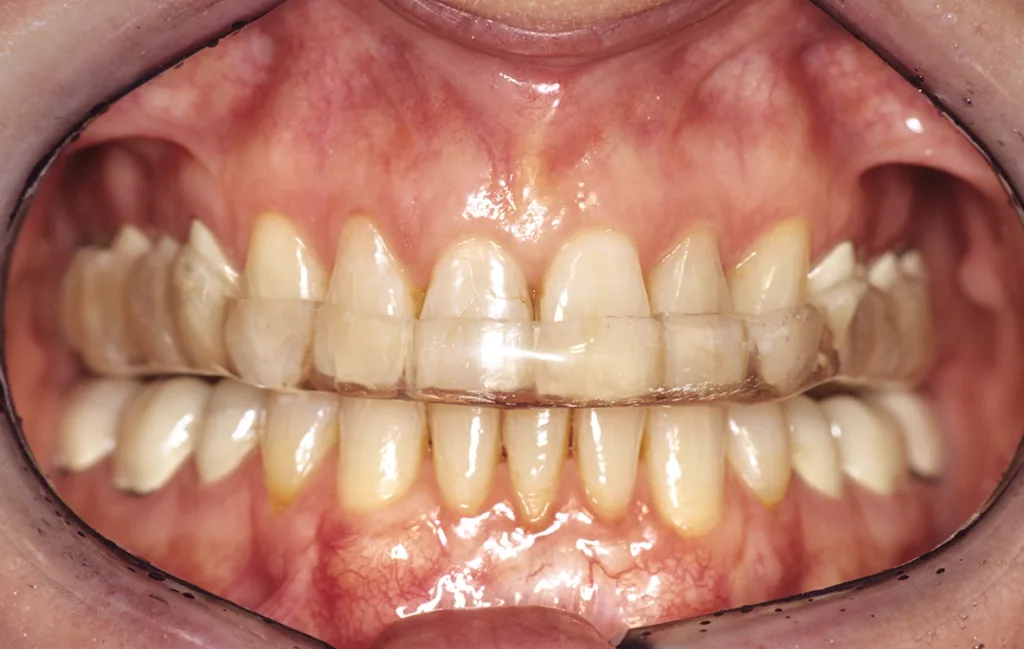

- Anfertigung einer Relaxierungsschiene im OK (bei Deck- oder Tiefbiss im UK) zur funktionellen Dekompensation mit frontalem Aufbiss und temporärer Entlastung im Molarenbereich durch vertikale Freistellung von 1 mm (GOZ 7000 ff.) (Abb. 5 bis 7).

Ziel ist die Dekompensation gewohnheitsbedingter Fehlfunktionen zur Entlastung, Revaskularisierung und Mineralisation des Alveolarknochens vor Implantation. Nach Durchführung der genannten Maßnahmen erfolgt bereits nach einer Tragezeit von vier bis sechs Wochen eine Entlastung von habituellen Gebrauchsmustern. Aus Hygiene- und Stabilitätsgründen werden die Schienen als Streuschienen in einer Stärke von ca. 1,5 mm gefertigt. Sie reichen jeweils bis zum Sechsjahrmolaren (Abb. 8).